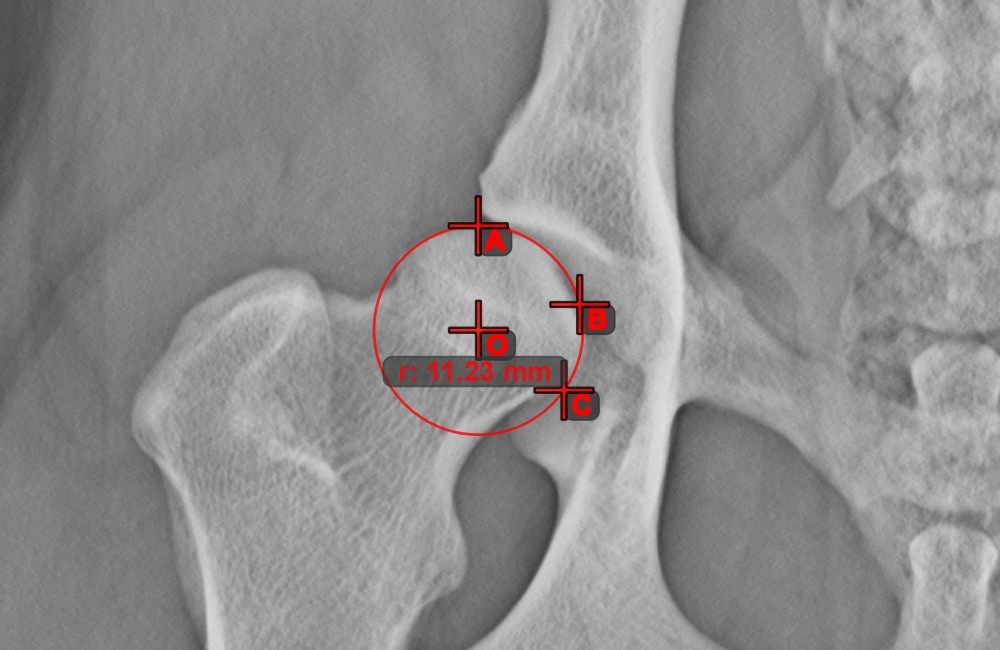

Circle from 3 Points¶

The Circle from 3 Points tool is a simple and effective way to create a circle from just three points.

Start by selecting the tool from the left toolbar and assign it to one of the available mouse buttons. Place the three points of the circle, or select the points from ones available on the scene. The circle will be automatically created based on the position of the three points. The origo of the circle will always be marked with O. The radius of the circle is automatically calculated.

Modify the position of the three points to change the radius of the circle by using the Select/Move Item tool.

Circle with Defined Radius¶

Draw a circle with fixed radius by using the Circle with Defined Radius tool. Only the position of the circle on the scene can be modified later.

Select the tool from the left toolbar and assign it to one of the available mouse buttons. Place the origo of the new circle on the scene or select an already existing point. Specify the desired radius of the circle and press OK

to complete the measurement.